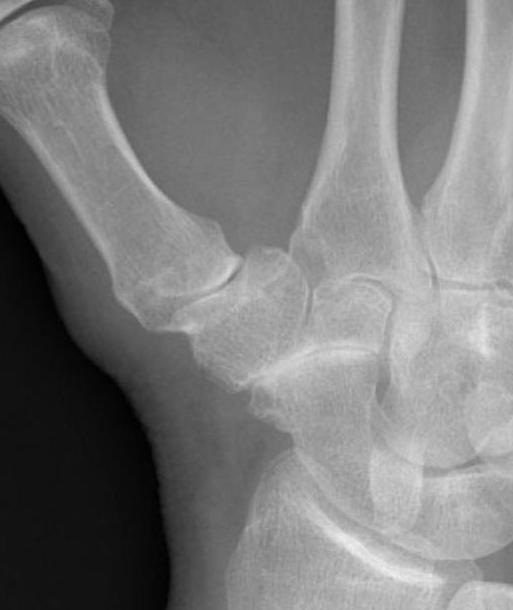

Isolated STT osteoarthritis

OA of the scapho-trapezium-trapezoidal (STT) joints

Third most common wrist osteoarthritis after CMC OA and SLAC wrist